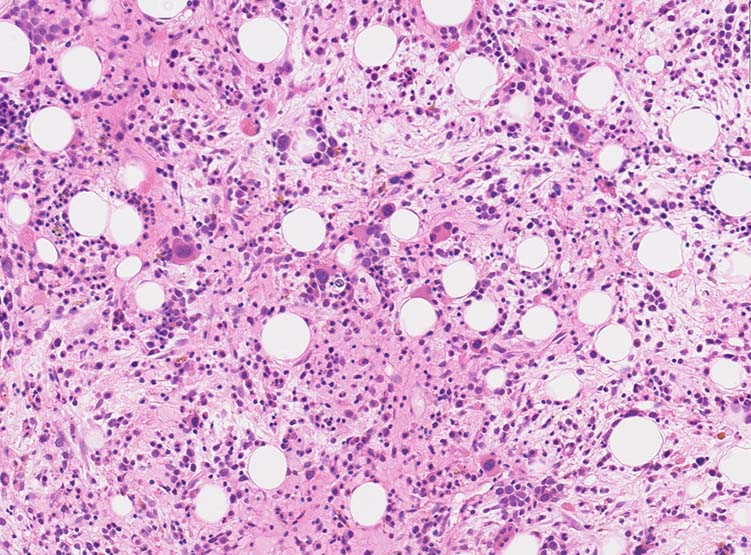

骨髄組織所見

正形成髄ないし過形成髄を呈する.

造血巣には, 巨核芽球と種々の成熟段階の異型巨核球が優位に増殖する. 両者の比率は症例によりさまざま.

小型巨核球が一様に増殖する症例では他のAML病型と形態的に区別ができないときがある.

巨核芽球とともに多数の成熟巨核球が増殖する症例もあるが, このときの成熟巨核球は一般に小型で, 低分葉核をもち異形成がめだつ.

微小巨核球が孤在性にあるいは集簇して多数認められる場合もある. クロマチンに濃染する1-2個の成熟核をもち成熟巨核球にみられる淡好酸性細胞質をわずかに有する細胞として見られる. 組織切片で巨核球系と同定するにはCD42b, CD61などの免疫染色が必要になる.

骨髄系, 赤芽球系の幼若細胞や異型細胞が混在することがあるが数はすくない.

骨髄線維症をともなうことがAML-M7の重要な特徴であるが, 必発ではない. 髄様の病変の症例がある.

弾性線維増殖であることが多いが, ところどころに膠原線維の増生を伴うことがある. (鍍銀染色, EVG, Azan染色で評価する)